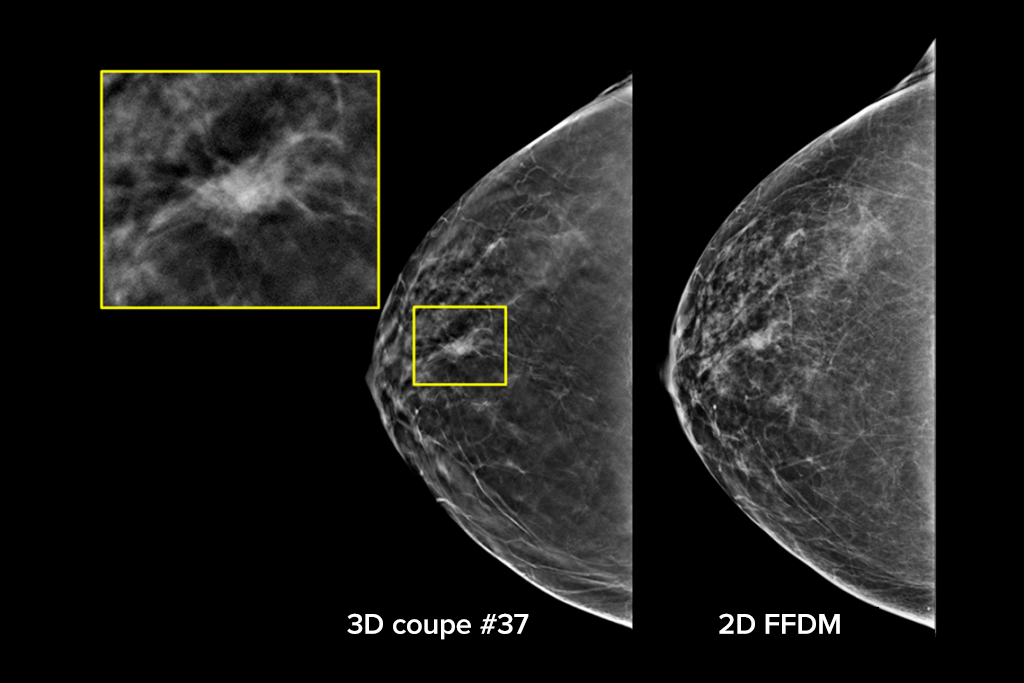

Images cliniques

Images cliniques d’une mammographie

Images cliniques d’une mammographie avec lésion suspecte

Images cliniques d’une mammographie sur un sein graisseux